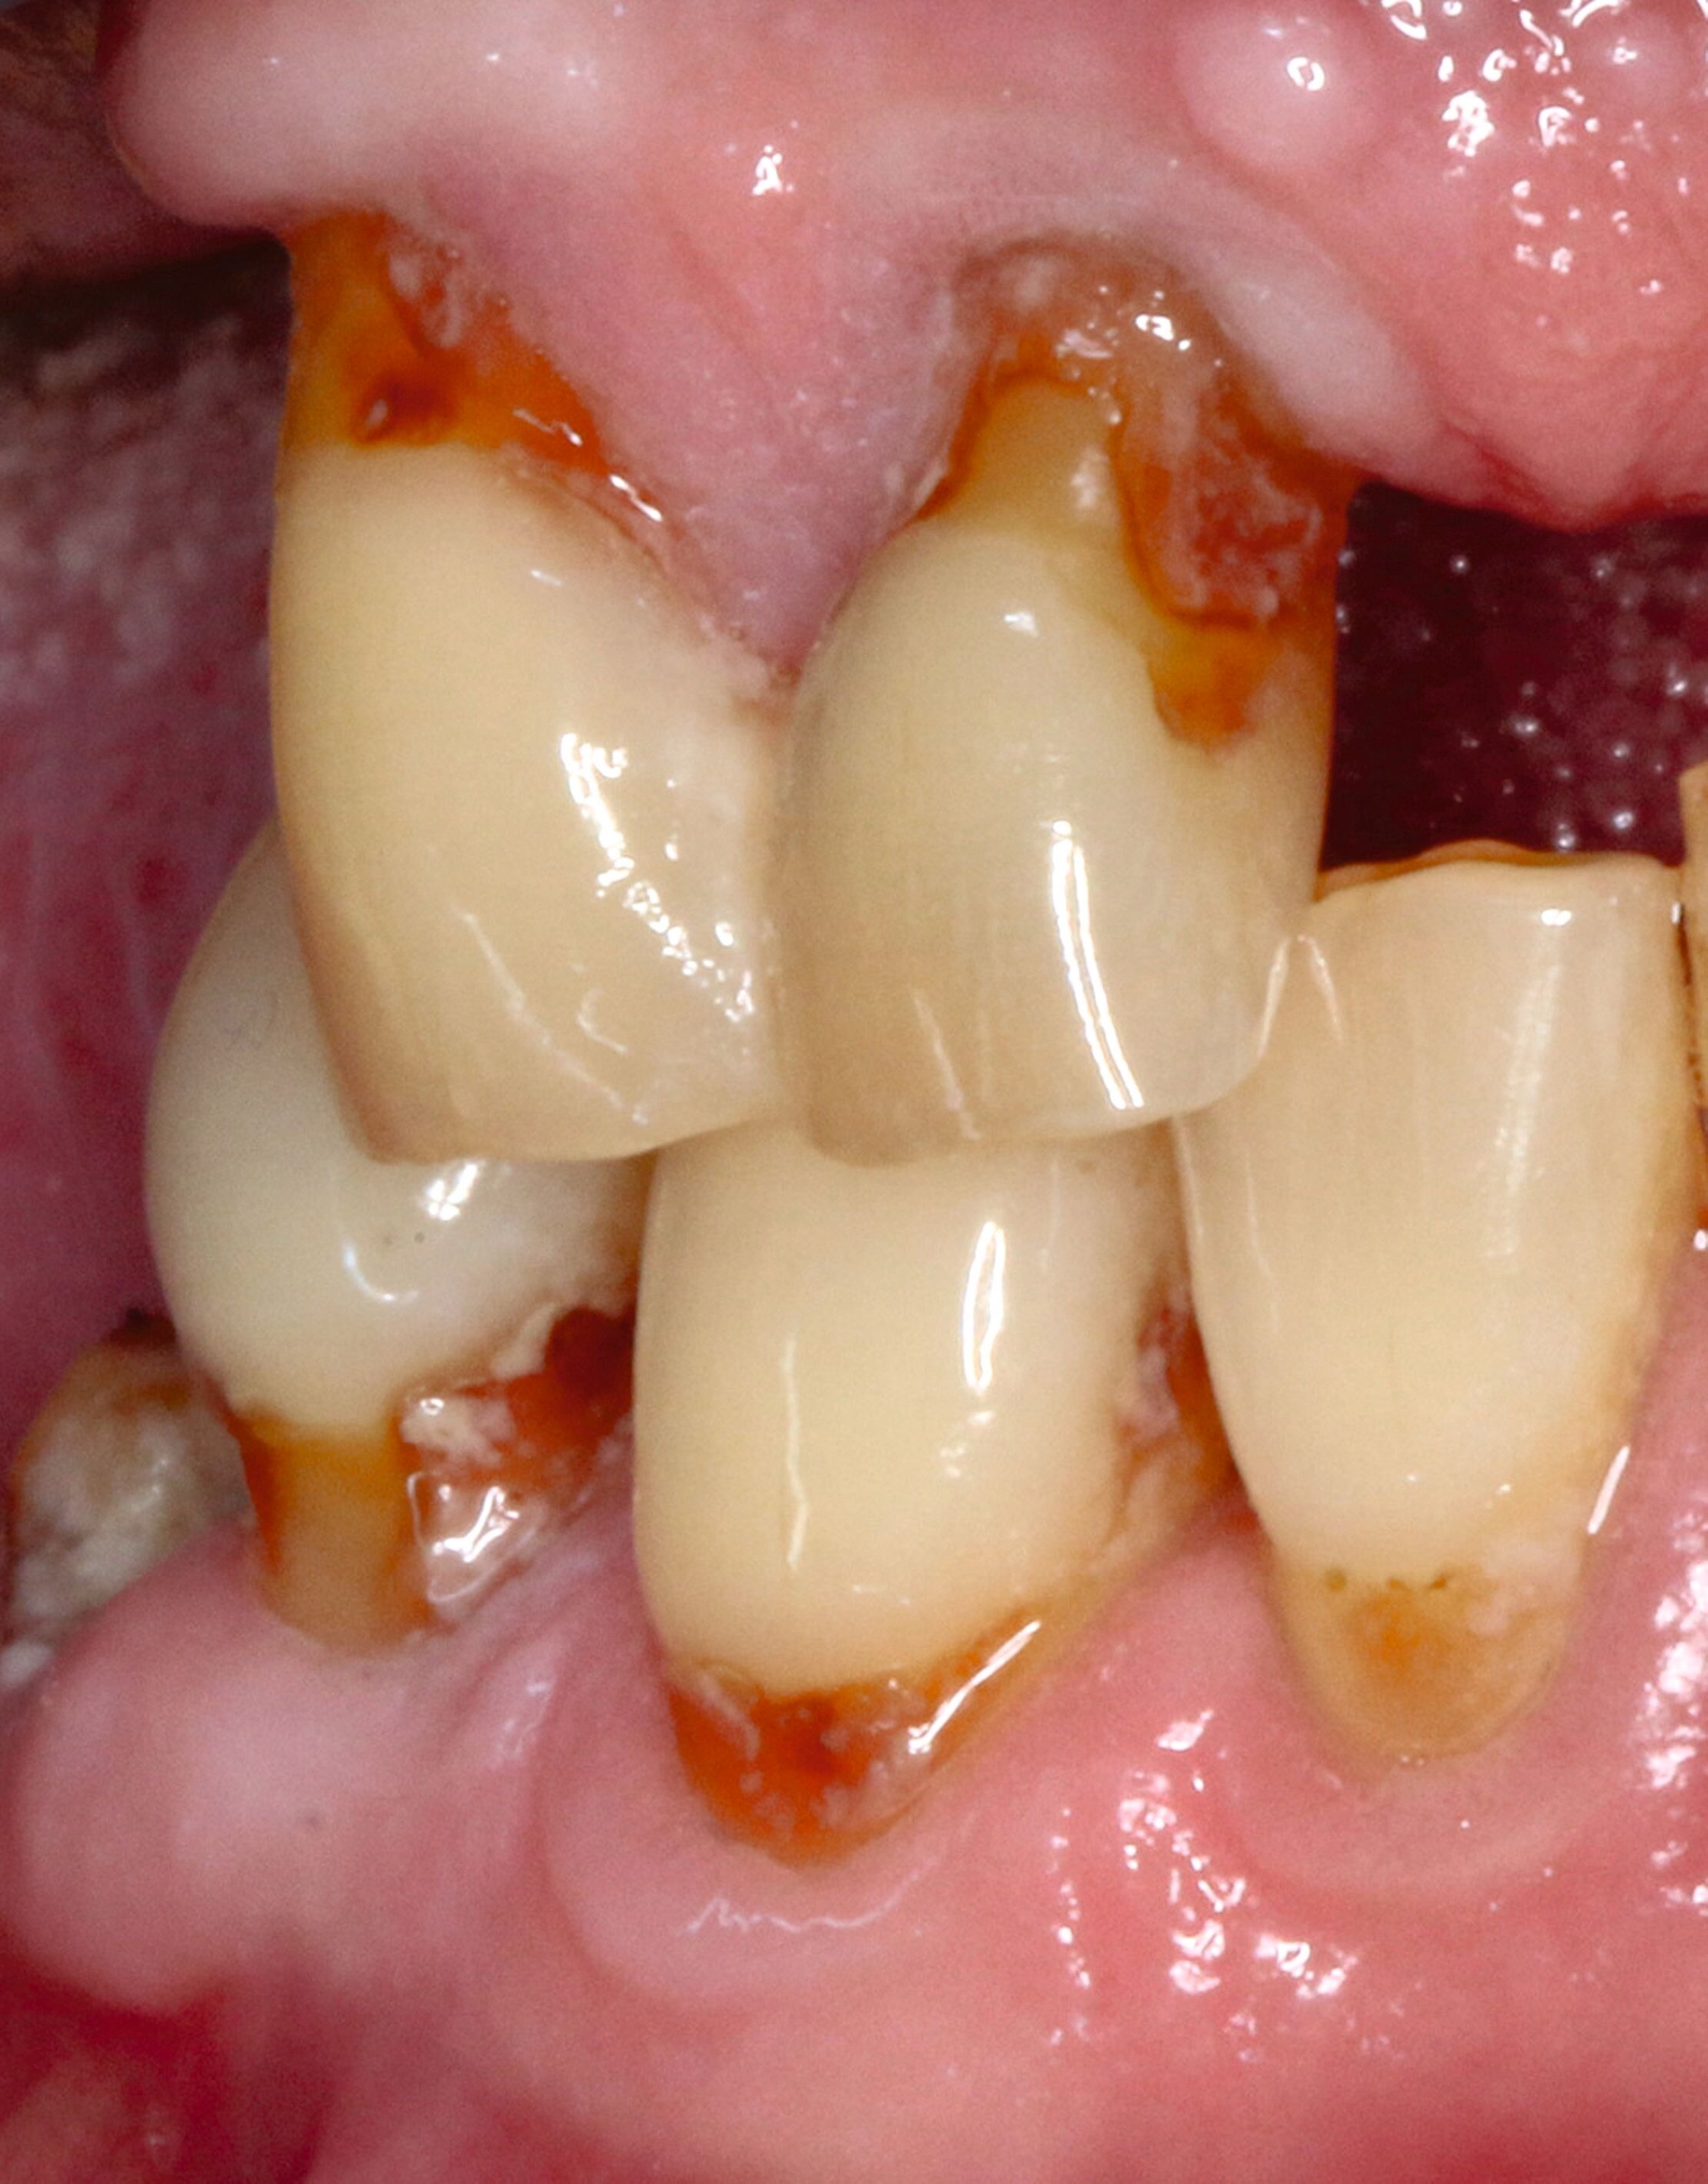

Abbildung 8 beschreibt einen Behandlungsablauf bei einer präexistenten Restauration an Zahn 23 mit deutlich sichtbarer Sekundärkaries zervikal und approximal (Abbildung 8a). Nach der Entfernung der alten Restauration (acht Jahre) zeigt sich das ganze schwer zu restaurierende Ausmaß des Defekts (Abbildung 8b).

Auf den ersten Blick ist klar, dass eine effektive Matrizentechnik hier schwierig wird, dass aber freies Schichten aufgrund der Nähe zur Gingiva ebenfalls keine gute Idee darstellt. Zur Kariesexkavation favorisieren wir schallschwingende, einseitig belegte Instrumente, die in der Regel keine Blutung provozieren, selbst wenn sie subgingival eingesetzt werden (Abbildungen 8c und 8d).

In solchen Fällen mit kaum zu kontrollierenden subgingivalen Rändern greifen wir vermehrt auf Stahlmatrizen zurück, die zervikal selbst bei extremen Fällen wie hier noch stabil nach subgingival geschoben werden können, die meist aber mit dem Finger fixiert werden müssen (Abbildung 8e). Bei dieser Technik ist es hilfreich, zunächst den subgingivalen Anteil mit einem gut fließenden Flowable zu füllen (Abbildung 8f), dann die Matrize abzunehmen, nachzufinieren, das Komposit sandzustrahlen und den breit angeschrägten Schmelz mit Phosphorsäure zu ätzen.

Dann wird der gesamte Bondingprozess wiederholt. Die erste Schicht zervikal steht zunächst nach labial über, dieser Kragen kann aber leicht mit einer Finierflamme wieder reduziert werden. Als Schichttechnik bietet sich im weiter koronalen Anteil an, die Fläche mit Flow zur besseren Benetzung auszukleiden, danach den Kern der Restauration aus modellierbarem Komposit zu gestalten und die oberste Schicht wieder aus Universal-Flow zu modellieren, weil dadurch eine blasenfreie Oberfläche erzielt werden kann (Abbildungen 8g und 8h).

Bei Fällen wie dem hier gezeigten ist die Ausarbeitung meist durch die erhebliche Zahnlänge erschwert, da man oft mit dem Kopf des Winkelstücks mit dem koronalen Anteil des Zahnes kollidiert. Hier ist alles erlaubt, was hilft, dieses Dilemma zu umschiffen. In diesem Fall hat es mit einem knospenförmigen Arkansasstein und Polierbürstchen gut funktioniert. Abbildung 8i zeigt die fertige Füllung.